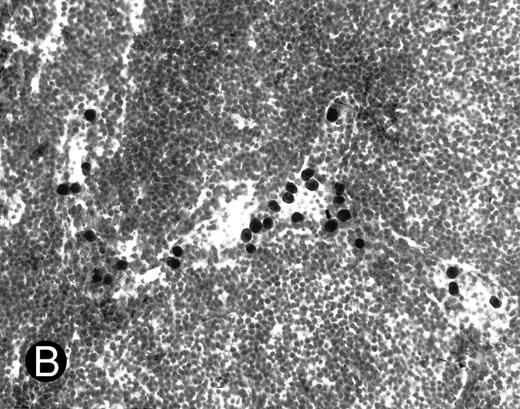

WEHI78/24 cells were preincubated with hybridoma supernatants and their binding to HEV in normal and inflamed PLN was assessed. As previously reported5 and reproduced here, WEHI78/24 cells failed to bind normal lymph node HEV, but WEHI78/24 cells bound well to HEV following CFA-induced inflammation (Figs 1 and 2). MoAb L11, but not class-matched, binding negative control MoAbs, blocked binding of WEHI78/24 cells to inflamed HEV by greater than 70% (Fig 2). For comparison, the effects of anti–L-selectin, αL, αM, β2, and α4 MoAbs, as well as two cell binding isotype matched control MoAbs (RB6-8C5 and 30G12), are presented in Table 1. None of the MoAbs used in these assays caused aggregation of WEHI78/24 cells.

WEHI78/24 cells bind to inflamed, but not normal PLN HEV. Binding of WEHI78/24 cells to normal (A) and CFA-inflamed (B) PLN HEV was assessed in modified Stamper-Woodruff frozen section assays. WEHI78/24 cells were added to freshly cut frozen sections and incubated for 30 minutes at 5°C under constant rotation. Nonadherent cells were washed away and the sections fixed and stained with thionine as described.14 A lower magnification of the normal lymph node is shown to illustrate lack of binding on multiple HEV.